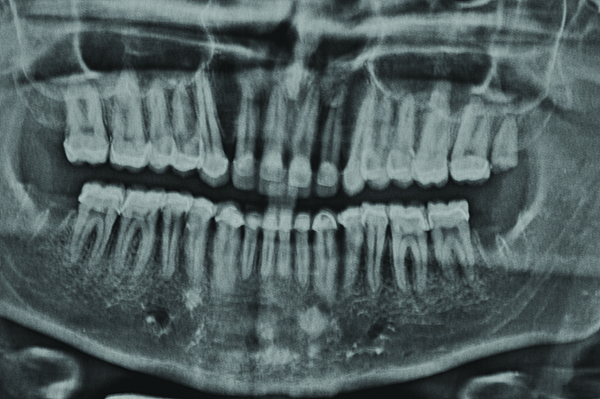

Figure 26. Postoperative OPG; note the vitality of the anterior teeth.

Figure 26

The final restorations depicted restoration of form, function, and beauty, with good harmony of restoration and the periodontium (Figure 19 through Figure 25). MIP was in harmony with CR, and right and left lateral excursion discluded all posteriors with anterior group function. The postoperative orthopantomogram (OPG) (Figure 26) shows the treatment done while maintaining the vitality of anterior teeth.